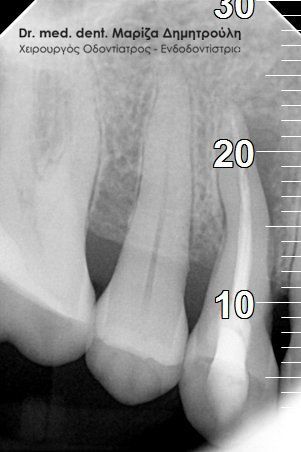

Περιστατικό – Στεφάνη / θήκη δοντιού

Ο ασθενής επισκέφτηκε το ιατρείο καθώς έσπασε ο άνω αριστερός προγόμφιος. Το συγκεκριμένο δόντι είχε μία παλία απονεύρωση δοντιού, η οποία περιοδικά έδινε συμπτώματα πόνου στον ασθενή. Μετά την κλινική και ακτινογραφική εξέταση του δοντιού αποφασίστηκε η επανάληψη της απονεύρωσης δοντιού και η προστασία του δοντιού με θήκη.

Ακτινογραφική εικόνα του δοντιού πριν την επανάληψη της απονεύρωσης

Ακτινογραφική εικόνα του δοντιού μετά την επανάληψη της απονεύρωσης